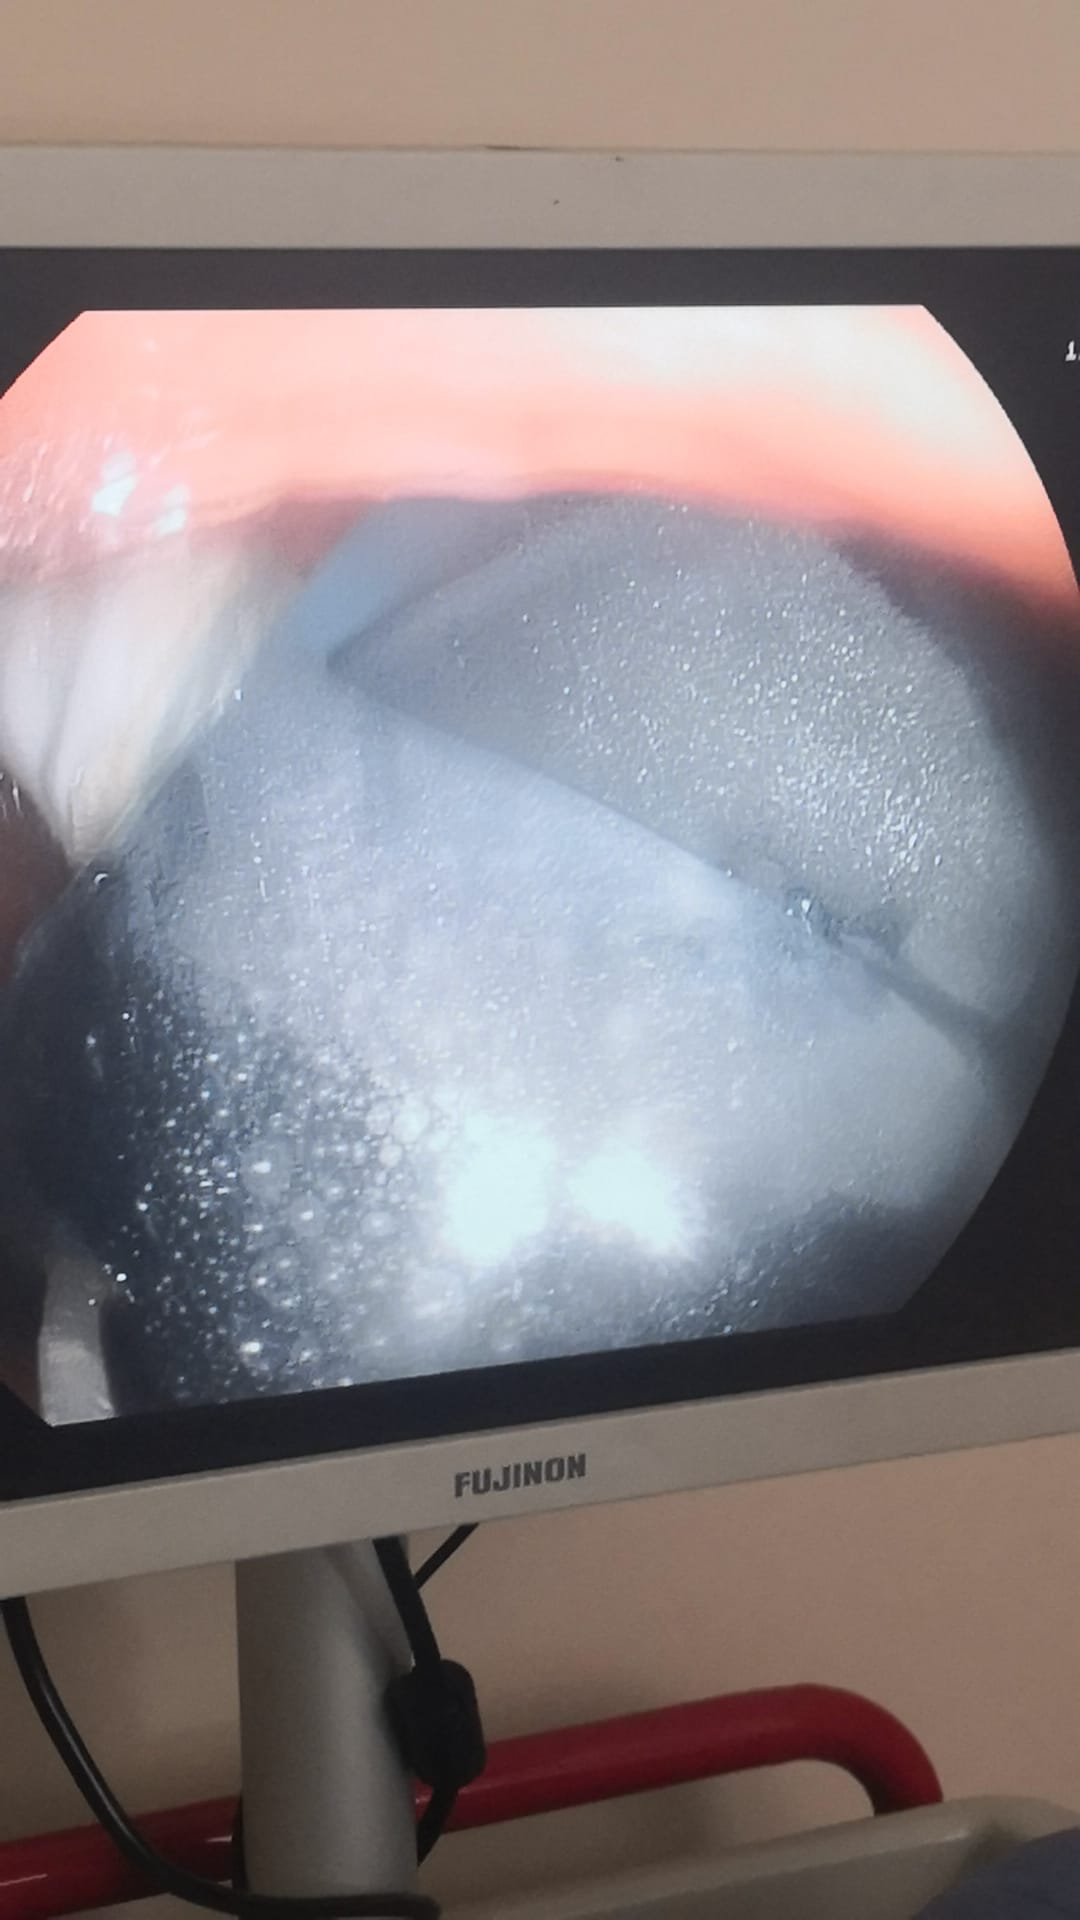

Photos